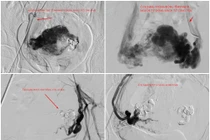

Nút mạch điều trị chảy máu tử cung do thông động tĩnh mạch hiếm gặp

Phụ nữ khi có triệu chứng ra máu âm đạo không đúng kỳ kinh, hay kéo dài bất thường, cần khám sớm để ngăn ngừa nguy cơ xuất huyết nặng, bảo vệ sức khỏe sinh sản.

Các bác sĩ khoa Chẩn đoán hình ảnh, Bệnh viện Đa khoa tỉnh Quảng Ninh đã phát hiện và kịp thời can thiệp nút mạch thành công cho nữ bệnh nhân 30 tuổi bị rong huyết kéo dài do thông động tĩnh mạch tử cung phức tạp, giúp kiểm soát chảy máu, cứu người bệnh thoát khỏi nguy cơ xuất huyết đe dọa tính mạng, bảo tồn tử cung, giữ trọn thiên chức làm mẹ.

Bệnh nhân là chị H. (30 tuổi) trú tại phường Cửa Ông, tỉnh Quảng Ninh. Khoảng một tuần trước khi nhập viện, chị H. xuất hiện tình trạng ra máu âm đạo bất thường, lượng máu tăng dần nên người bệnh đến viện thăm khám.